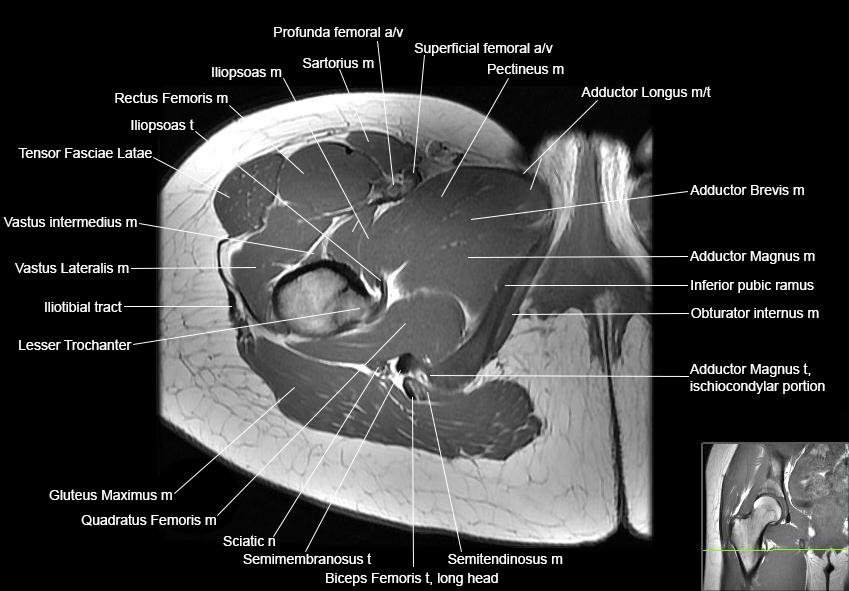

Hip

Basic Hip MRI

MRI Hip Anatomy

Scroll using the mouse wheel or the arrows